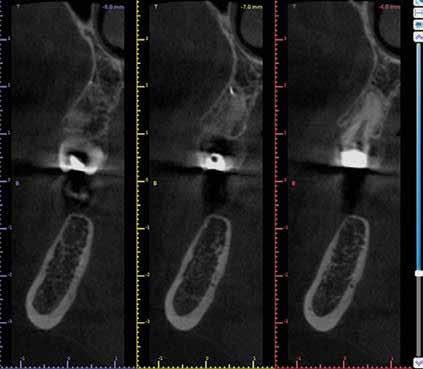

KOMPLEX FOGAZATI REHABILITÁCIÓ

A fogazat elhasználódása alatt azoknak a degeneratív folyamatoknak az összesített hatását értjük, melyeken az élet során a szervezet keresztülmegy. Ezek lehetnek a fogérintkezések közben fellépő mechanikai erők (abrázió, attríció), endogén vagy exogén eredetű savas közegek által kiváltott kémiai behatások (erózió), kariogén baktériumok által okozott pathológiás folyamatok és parodontális elváltozások, valamint iatrogén ártalmak.

A felnőtt páciensek kezelése során általában egyszerre több ellátásra szoruló elváltozást is diagnosztizálhatunk: hiányzó fogak, kopott fogazat, esetleg régi, nem megfelelő, sérült fogpótlások, rendellenes helyzetben lévő fogak stb… Ezen páciensek kezelésekkel kapcsolatos kérései mindig az esztétikai vagy a rágással kapcsolatos kívánságaik kielégítését szolgálja. A kezelések során a fogorvosoknak nem csak a páciensek kéréseinek teljesítésére, hanem ezzel egyidejűleg a fogazat általános megjelenésének és funkciójának lehetőség szerinti javítására is törekedniük kell. Mindemellett a lehető legtöbb saját foganyag megőrzését és az évek során elvesztett kemény- és lágyrészek pótlását (pl.: hiányzó fogak, sorvadt állcsontgerinc, lágyszöveti defektusok) is szem előtt kell tartaniuk, úgy, hogy közben egy hosszú távon fenntartható eredményekkel járó kezelési tervet állítanak össze. Ezek mindig összetett esetek. Annak érdekében, hogy a fentiekben megfogalmazott összes kezelési célt teljesíteni tudjuk, interdiszciplináris megközelítésre van szükség. Az ilyen komplex rehabilitációs kezeléseket „fogászati megfiatalításnak” nevezzük. Ezeknek a beavatkozásoknak lényege az elhasználódott fogazat biológiai szempontokat figyelembe vevő minimál invazív módon történő helyreállításában rejlik, mely folyamat végére a páciensek fogai visszanyerhetik fiatalkori megjelenésüket.

A rehabilitációs kezeléseknek a célja, hogy a páciensek a lehető leghosszabb időn keresztül képesek legyenek mosolyogni és rágni. A protetikai kezeléseket végző fogorvosoknak helyre kell tudni állítaniuk a fogívek szabályos lefutását és az alsó és felső fogív között megfelelő interokkluzális érintkezéseket kell létrehozniuk. Így lehet csak az ellátás befejezését követően elért végeredmény biológiai szempontokat figyelembe vevő esztétikáját, funkcionális megfelelőségét, hosszú távú fenntarthatóságát biztosítani.

Nagyon fontos, hogy már a kezelések elején meghatározzuk, hogy melyek azok a hiányzó fogak, amelyeket a későbbiekben pótolni szeretnénk, valamint helyesen diagnosztizáljuk a kariológiai, endodonciai vagy parodontológiai okok miatt ellátást igénylő elváltozásokat. Szintén kiemelt jelentőséggel bír a fogak megtarthatóságának kiértékelése. A kezelési terv felállítása során tisztában kell lennünk azzal, hogy mely fogak alkalmasak fogpótlások ideiglenes vagy végleges elhorgonyzására.

A preprotetikai fázisban el kell látnunk a diagnosztizálásra került kórfolyamatokat, megfelelő pozícióba kell állítanunk a megtartani kívánt fogakat, pótolnunk kell az elvesztett csontállományt, valamint gondoskodnunk kell az íny megfelelő állapotáról. Ha szükség van rá, úgy a foghiányok pótlására szolgáló dentális implantátumok is ebben a fázisban kerülnek behelyezésre. Általánosságban elmondható, hogy azokat a kezeléseket, amelyek befejezése biológiai okok miatt hosszú időt vesz igénybe (pl.: fogszabályozás, csontpótlás, implantáció), a lehető leghamarabb érdemes elkezdeni.

A fogszabályzó kezelések egyik legfontosabb célja, hogy elérjük a lehető legharmonikusabb interokkluzális fogérintkezéseket, továbbá az állcsont relációs helyzetének frontális és szaggitális síkban is megfelelőnek kell lennie. A fogszabályzás befejezésekor a fogpozícióknak nem orthodonciai, hanem protetikai szempontok szerint kell ideálisnak lenniük. Az Invisalign ClinCheck szoftver (Align Technology) segítségével a protetikus az orthodontussal együtt meg tudja határozni azokat a végső fogpozíciókat, amelyek a lehető legjobb végeredmény biztosításához elengedhetetlenek. Bizonyos klinikai paramétereket, mint a fogak klinikai koronájának nagyságát, az egyes fogak fogíven belüli optimális pozícióját, a fogívek egymáshoz viszonyított helyzetét, a fogak között látható rések nagyságát, a frontfogak tengelyének dőlését, az overjet és overbite mértékét már a kezelések megkezdése előtt pontosan definiálni kell. Ezeket az adatokat viszont csak a tervezett végleges fogpótlás ismeretében lehet meghatározni, ezért van szükség az orthodontus és a protetikus szoros együttműködésére.